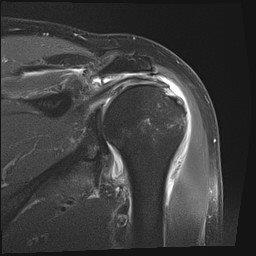

Die Diagnosestellung basiert auf der Krankengschichte (unfallbedingte Verrenkung, einmal oder mehrfaches Auskugeln ...), der Untersuchung der betroffenen Schulter sowie der bildgebenden Diagnostik. Hierbei sind sowohl konventionelle Röntgenbilder, als auch Schnittbildverfahren (MRT – Kapselschaden, CT – knöcherne Verletzung, Defekte) hilfreich. In komplexen Fällen müssen diese durch intraartikuläre Kontrastmitteluntersuchungen ergänzt werden.

69-jähriger Patient mit linkseitiger Schulterluxationsverletzung. Bei älteren Patienten kommt es im Rahmen der Schulterverrenkungen häufiger zu Sehnenabrissen am Oberarmkopf. Trotz der Einrichtung des Gelenkes kann der Arm nicht wieder gut bewegt werden. Erst die operative, in diesem Falle rein arthroskopische Rekonstruktion der Sehnen und deren Einheilen ist eine Schultergelenksbewegung wieder gut möglich.